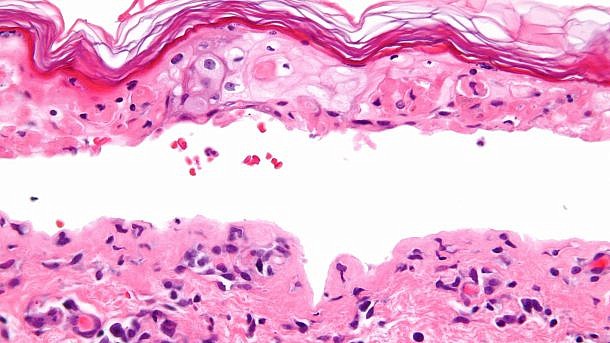

ידוע כי תרופות אנטי אפילפטיות (AEDs – Antiepileptic drugs) עשויות לגרום תסמונת סטיבן-ג’ונסון (SJS – Stevens-Johnson syndrome) ולנמק עורי רעיל (TEN – Toxic epidermal necrolysis), שהן שתי תופעות עוריות חמורות. עם זאת, מידע המשקף את המציאות נותר מוגבל, בייחוד בנוגע לילדים.